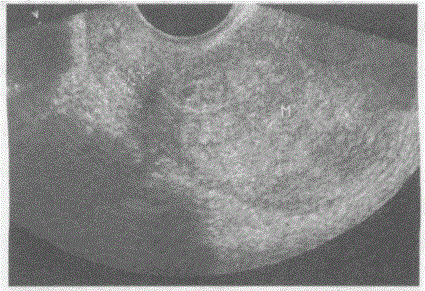

问题 临床资料:女,62岁,自述绝经10年,阴道不规则出血半年。 超声综合描述:经阴道扫查子宫后位,增大,子宫内膜不均匀性增厚,与子宫肌层分界不清,侵及肌层深度>50%,接近浆膜层,CDFI:内可见丰富动、静脉血流信号,呈低阻型动脉频谱。见下图及彩图。 {图1} 超声提示:

选项 A.子宫内膜癌(侵及肌层>50%) B.子宫肌瘤 C.子宫腺肌症 D.子宫内膜腺瘤样增生

答案 A